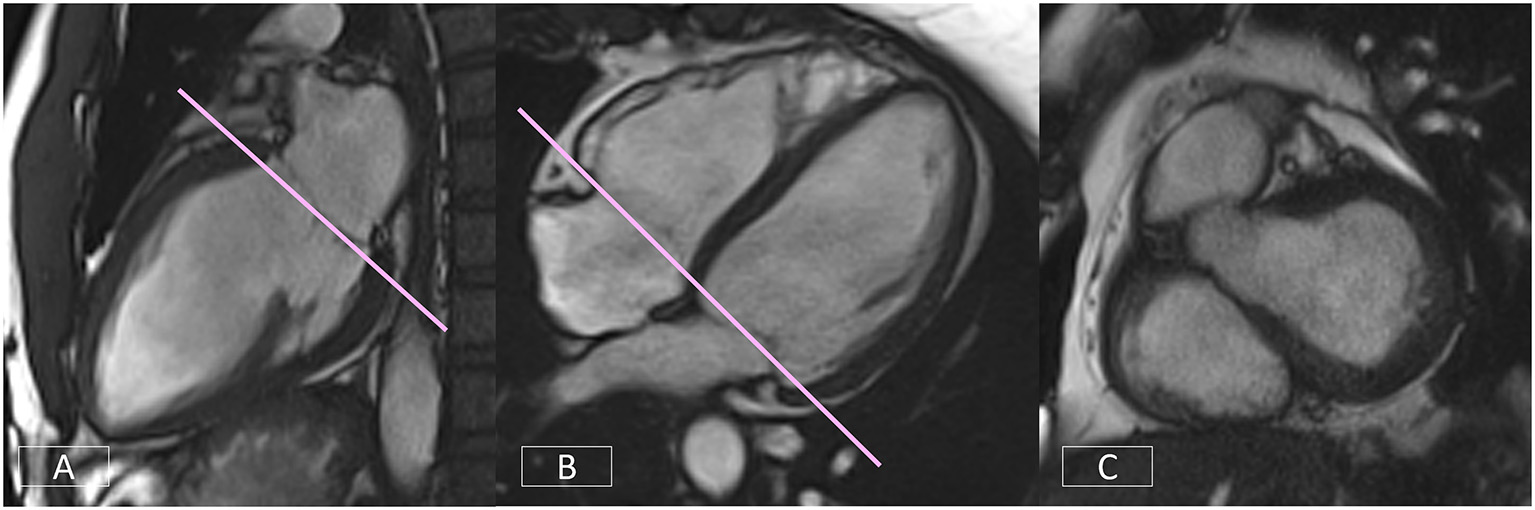

Left Ventricular Short Axis—Accurate Positioning of the Basal Slice

Correct positioning of the basal slice of the LV SAX stack can significantly improve the accuracy and reproducibility of volumetric analysis. A consistent and reproducible method of positioning this slice is critical. As outlined in Section Clinical Cardiovascular MR: What do we See and why do we Need it?, both the LV VLA (Figure 9A) and 4-chamber (Figure 9B) views must be used to ensure the basal diastolic phase slice is positioned parallel to the mitral valve annulus, avoiding atrium and with an even amount of myocardium around the blood pool (Figure 9C).

Figure 9

Accurate positioning of the basal slice of the LV SAX series requires the use of both the LV VLA (A) and the 4-chamber (B) views to ensure the basal diastolic phase slice is positioned parallel to the mitral valve annulus, avoiding atrium and with an even amount of myocardium around the blood pool (C).

If the image position is not correct, simple corrections are shown in Figure 10 (top row). If the basal diastolic phase slice includes atrium (Figure 10A), the slice must be repositioned toward the apex (Figure 10B). If there is an inconsistent amount of myocardium (Figure 10C), the slice angle is tilted on the LV VLA view (Figure 10D).

Figure 10